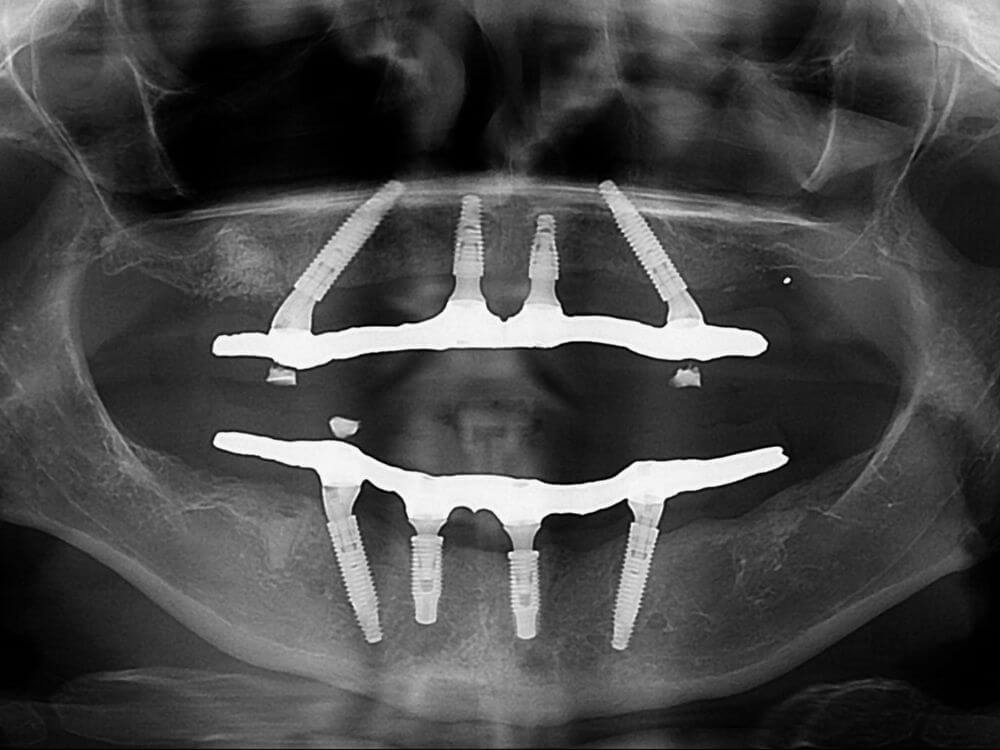

Com apenas 4 implantes é possível instalar uma prótese fixa com todos os dentes da arcada. Não necessita enxerto ósseo. Solução rápida e altamente eficaz.